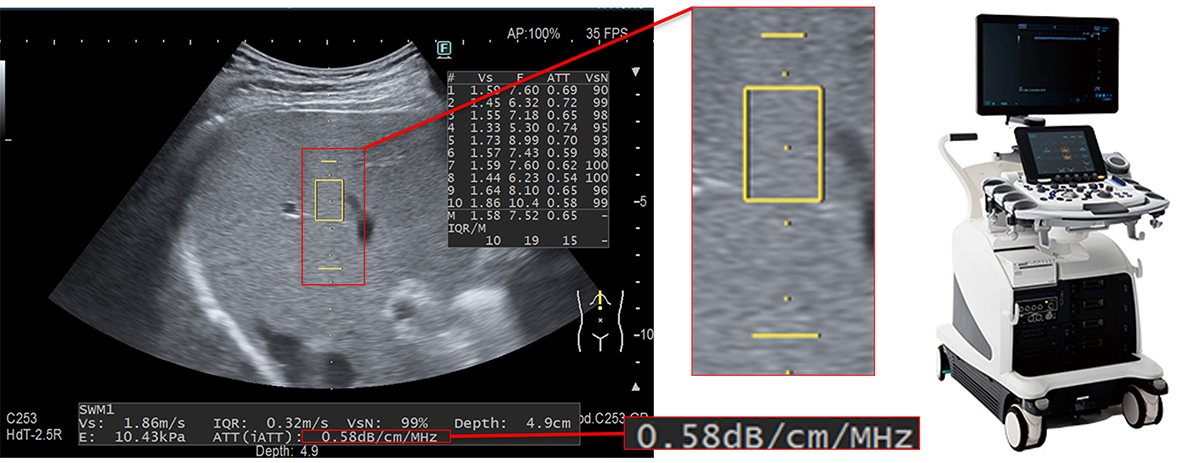

このようなことから、深部での信号劣化の要因の排除や演算方式の見直しをすすめ、アルゴリズムの改善を行った。改善したATTは、ARIETTA850/750シリーズにおいて、iATTとして搭載される(図1)。

図1 ARIETTA 850外観とiATT*2

- *2 画像は現在開発中のものです。製品と異なる場合があります。